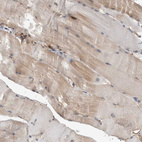

Immunohistochemical staining of human tonsil shows strong cytoplasmic positivity in germinal center cells.